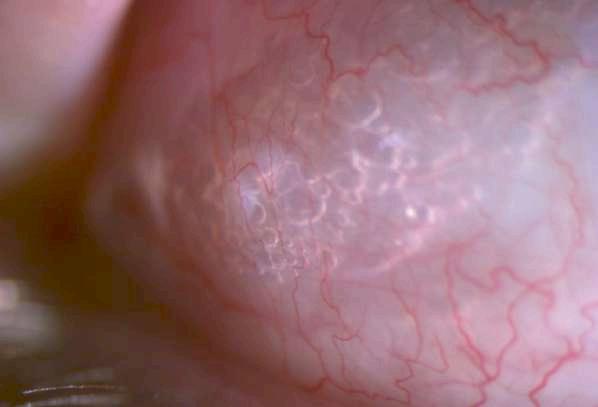

3.B. MELANOMA AMELANÓTICO

Caso aportado por Dr. Osvaldo Weisse

ü Imagen C: Lesión sólida ligeramente irregular, homogénea, de reflectividad media baja con elementos de vascularidad en su interfase. Altamente consistente con melanoma de coroides

ü Mujer 57 años consultó en policlínico por cuadro de disminución de la agudeza visual de hemicampo superior del ojo derecho, indoloro de 1 mes de evolución

ü Imagen B: Subyacente al DR hay una lesion sólida dependiente de la coroides, irregular en base (18.8mm) y altura (1.63)

C

A B